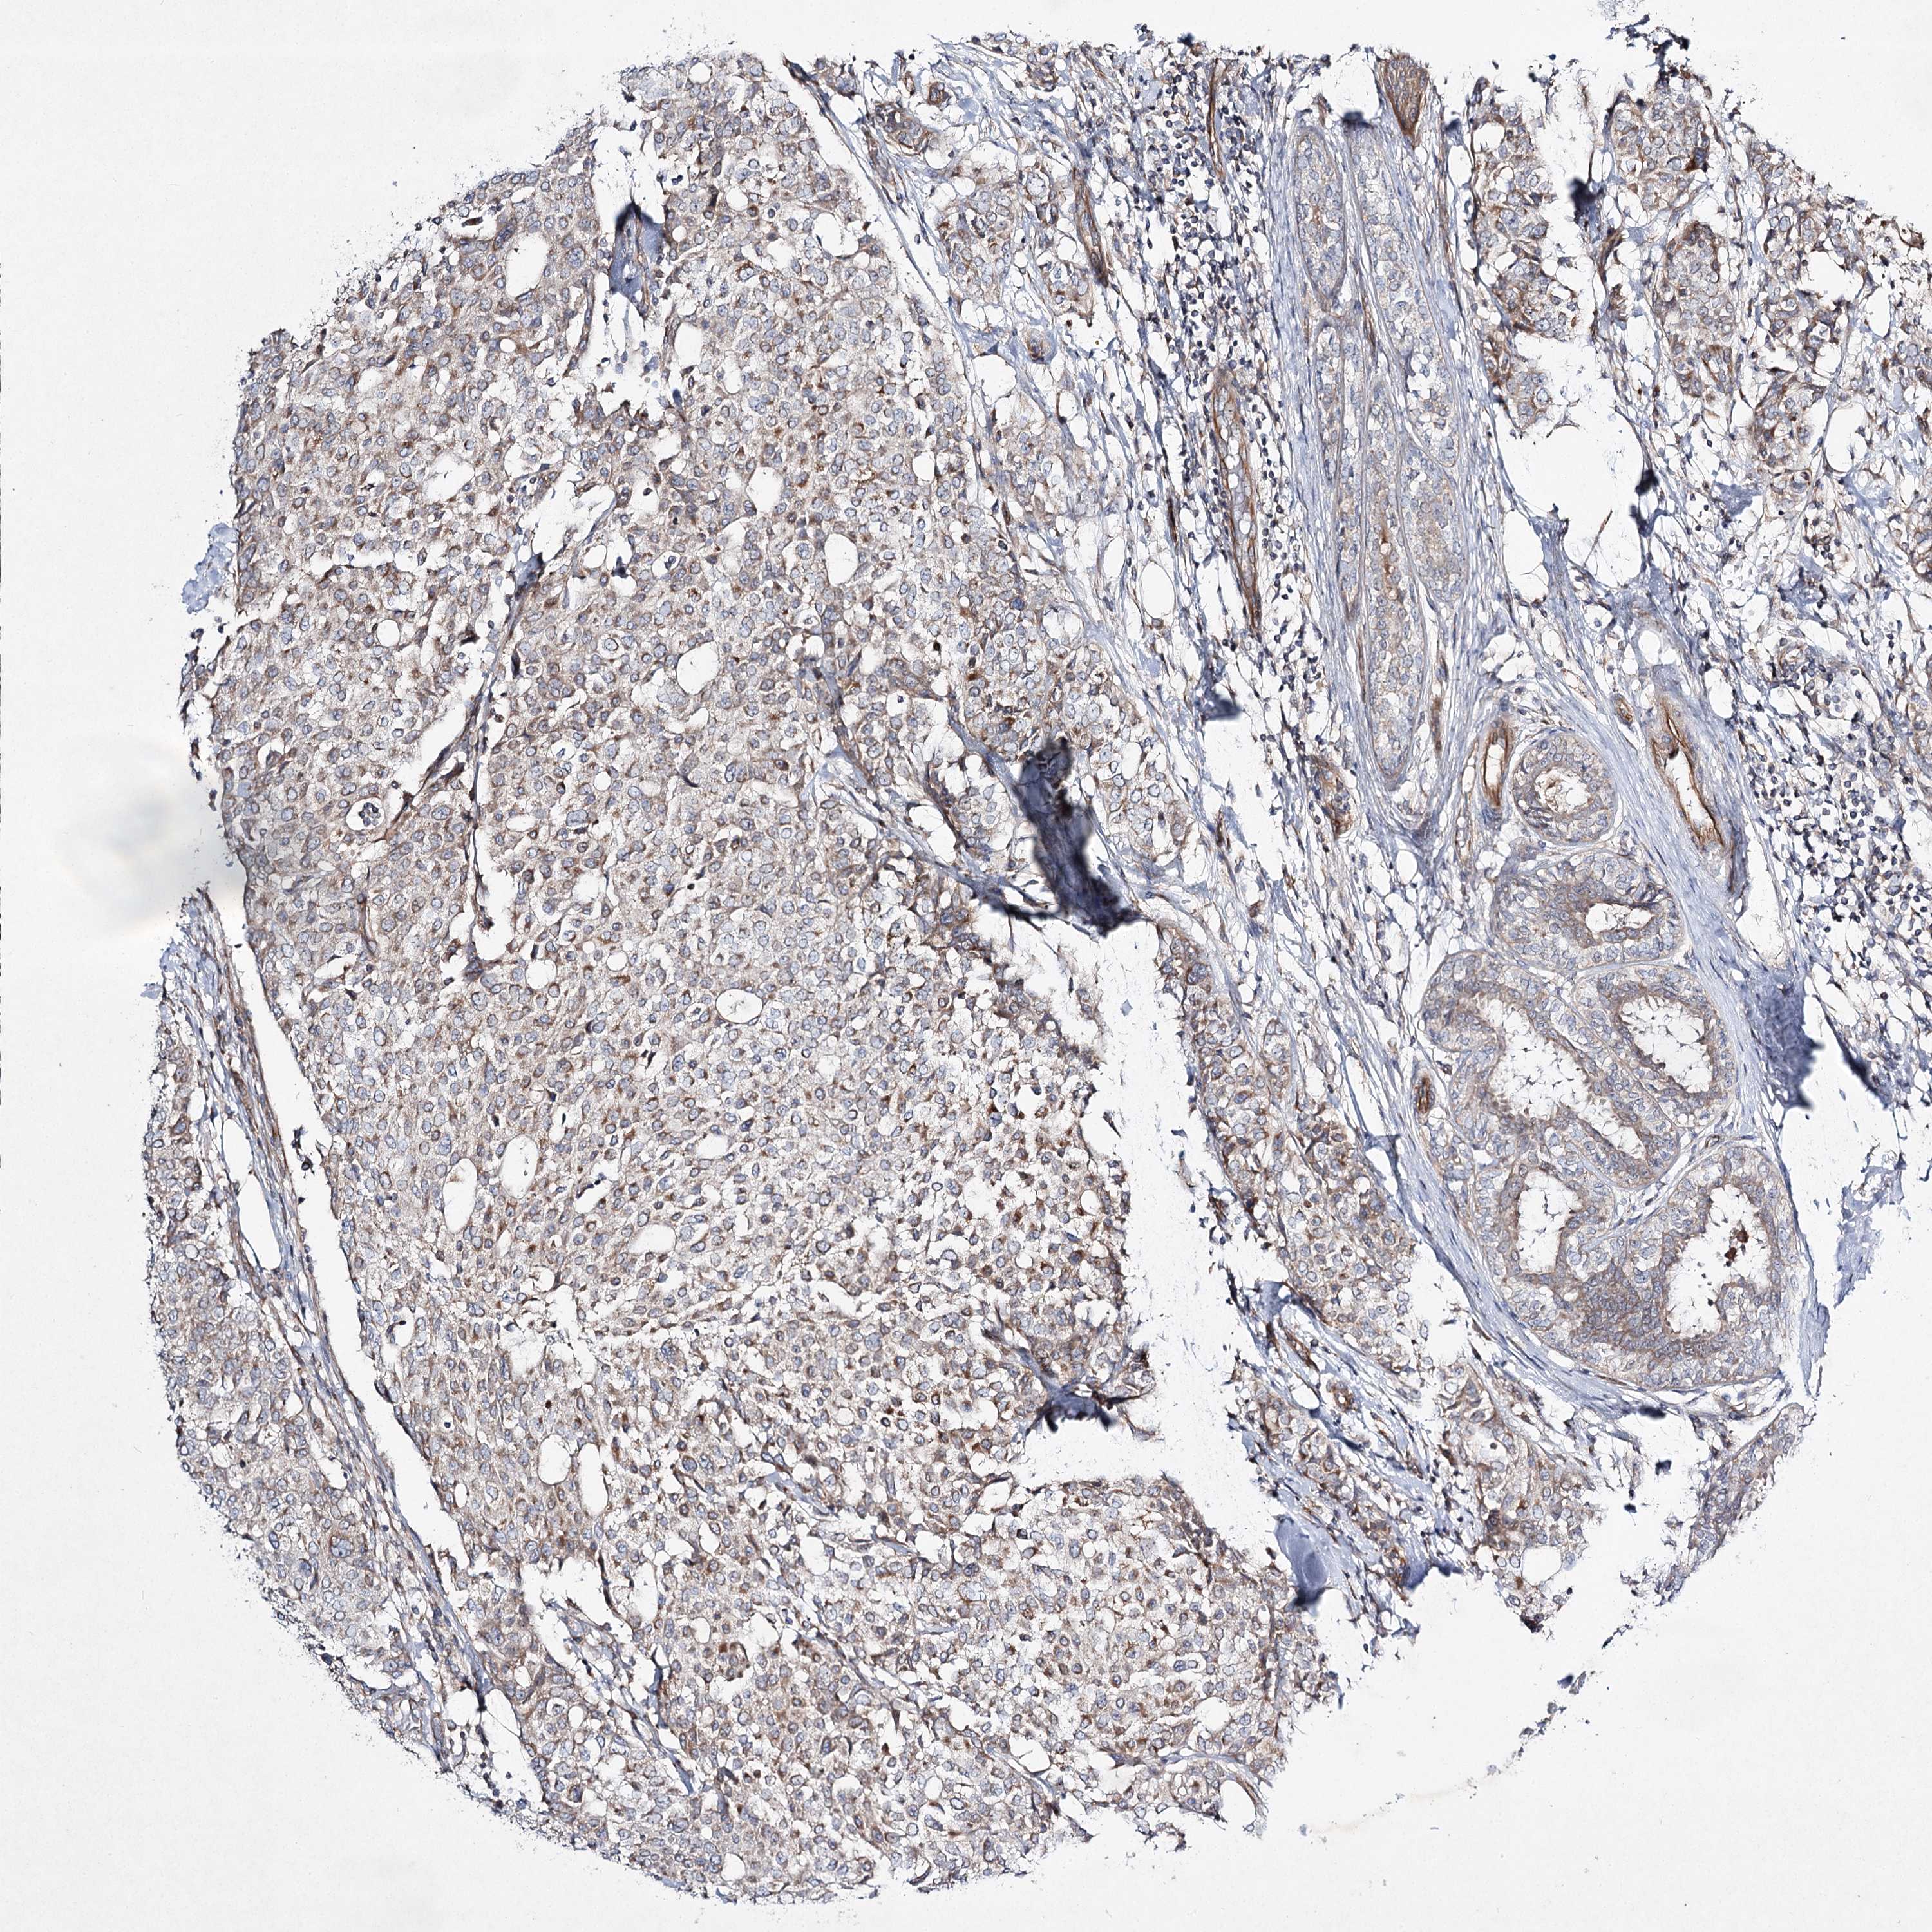

CANCER BREAST CANCER Show tissue menu

BRCA TCGA BRCA VALIDATION PROTEIN EXPRESSION